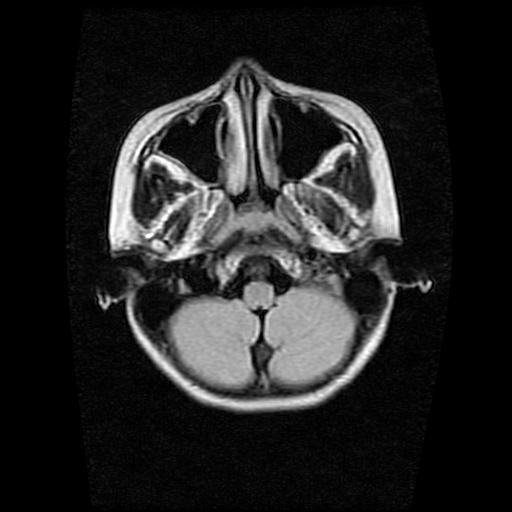

9岁女孩,三岁时诊断为癫痫,一直服丙戊酸钠,现患者一般情况良好,家长复查核磁片,看能否停药..

巨脑回